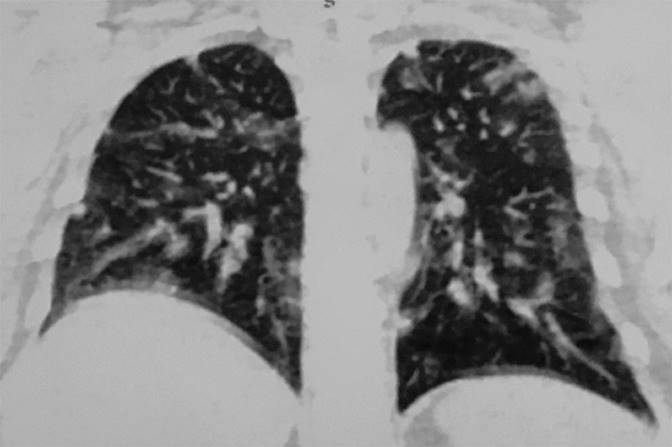

La tomografía toracoabdominopélvica simple y contrastada reportó: múltiples nódulos pulmonares de distribución dispersa, hígado y ovarios normales. La tomografía de cráneo simple y contrastada no informó anormalidades. Figura 2

Figura 2 Tomografía toracoabdominopélvica con múltiples nódulos pulmonares de distribución dispersa y de cráneo simple normal.

En este caso se trató de un coriocarcinoma por lo que luego de diagnosticarlo y cohibir el sangrado y empezar la reposición sanguínea hay que determinar la extensión del tumor con una radiografía de tórax, tomografía computada y resonancia magnética que, en este caso, permitió estadificar el tumor en estadio III, por su invasión al pulmón, con múltiples focos de metástasis.